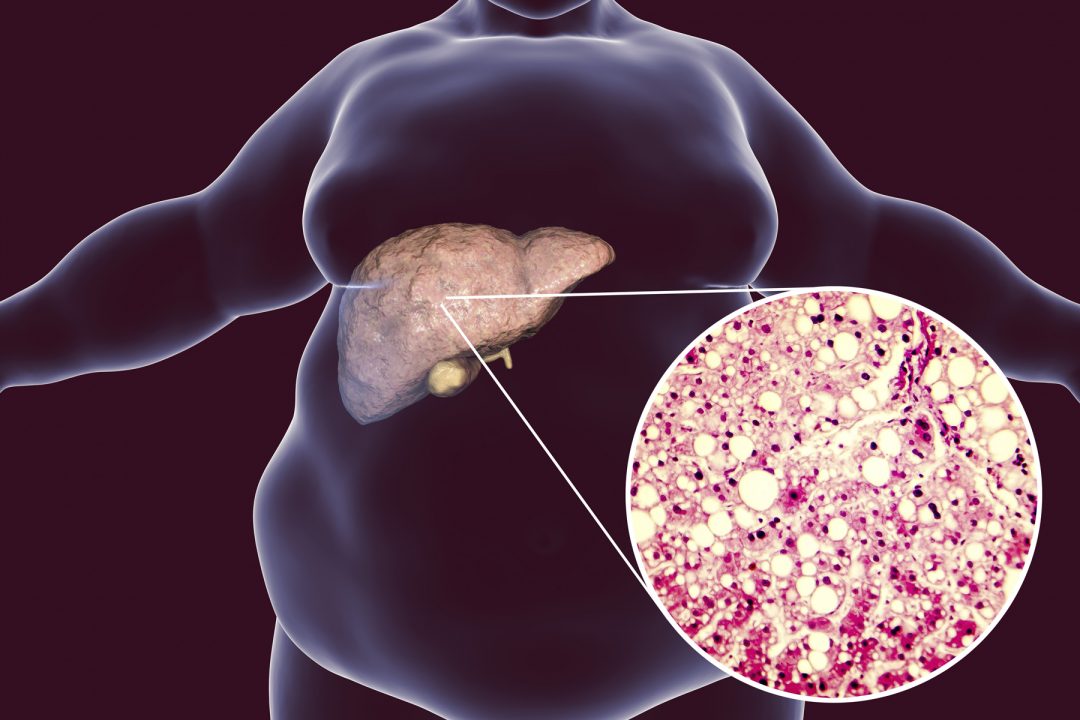

NAFLD is emerging as a public health issue worldwide. It is estimated that prevalent cases will increase 21% by 2030, from 83.1 million to 100.9 million. NAFLD is more commonly found in people with type-2 diabetes, and is linked to obesity, insulin resistance and atherogenic dyslipidemia. NAFLD refers to excess fat accumulation in the liver, in the absence of excessive alcohol consumption. Alcohol consumption of less than 30 g (3.75 units) per day for men is used as the cut-off to diagnose NAFLD. As an increasing global health issue, this study and its findings may be a promising area for further research.

Dr Kristina Groti Antonic shared that, “improvement of NAFLD grade was a result of improved insulin resistance, reduction in body mass index and body weight, along with changes in body composition. As we know, testosterone increases lean body mass at the expense of fat mass, either alone or in combination with behavioral and lifestyle modifications. Testosterone with its anti-inflammatory effects also reduced chronic inflammatory state in the liver. Our study shows that testosterone therapy could be used as a suitable therapy for obese men living with non-alcoholic fatty liver disease, and therefore the findings can be used to tackle this growing pandemic.”